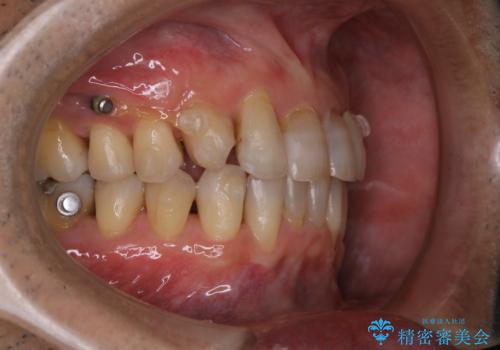

- マウスピース矯正中(インビザライン)に着色落としをしたいとのことでした。PMTC60分コースを行いました。

PMTC(保険外治療)は、毎日の歯磨きで落としきれない汚れや、コーヒ、紅茶・タバコのヤニなどの着色も除去します。目には見えない歯と歯の間・歯肉の境目・インビザライン中はアタッチメント周囲などに残っているプラーク(歯垢)もしっかり取り除きます。PMTCでは専門的な機械や材料を使用して、徹底的に汚れを除去するため、虫歯・歯周病・口臭予防などにつながります。